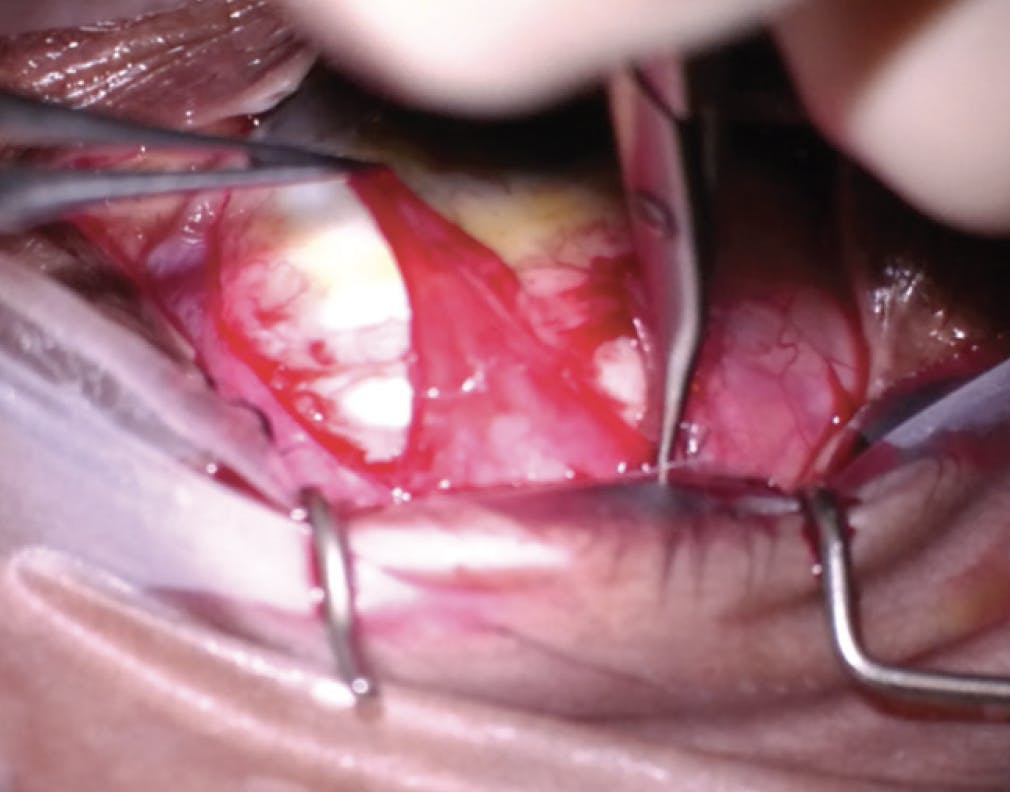

- Step No. 2: Three spaces were dissected. First, the conjunctival layer was incised linearly above the bleb space. Care was taken to free the conjunctiva from the Tenon capsule (Figure 5). Next, this capsule was dissected superior to the bleb to create a tongue of Tenon membrane (Figure 6). Finally, dissection inferiorly and under the bleb was performed to create space (Figure 7).

Figure 5. The bleb revision is initiated with dissection through and under the superior conjunctiva.